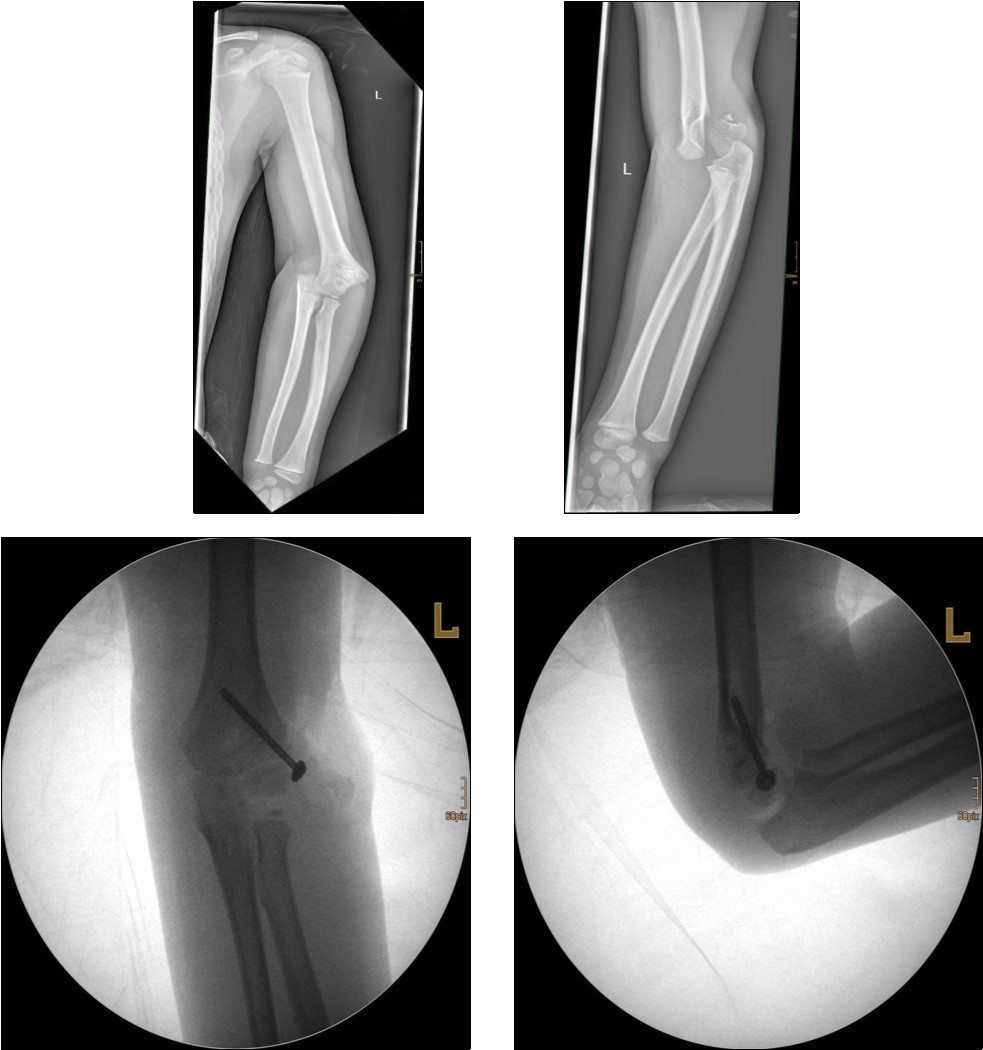

Non-displaced and stable fractures may be treated by cast immobilization with close follow-up, but fractures displaced >2 to 3 mm may indicate surgical fixation 7, 8. Surgical treatment can be done either by closed reduction and percutaneous osteosynthesis or open reduction and osteosynthesis. Figure 3.

Figure 3.9 year old male patient with a elbow dislocation and a dislocated left lateral condyle fracture which was treated by open reduction and osteosynthesis with a screw (personal collection)

9 year old male patient with a elbow dislocation and a dislocated left lateral condyle fracture which was treated by open reduction and osteosynthesis with a screw (personal collection)